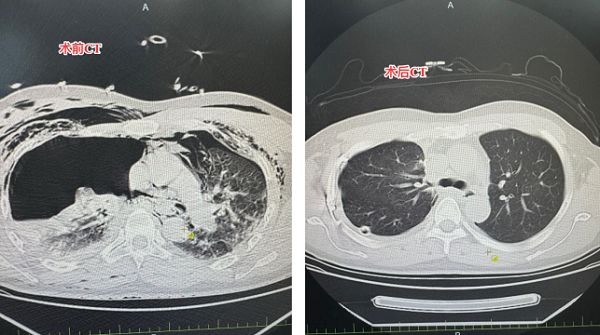

术后,患者被转入重症监护室严密监测。支气管断裂吻合术后最易出现吻合口漏或狭窄,医护人员每两小时听诊呼吸音,术后第二天复查胸部CT,确认吻合口愈合良好。术后第六天,患者成功脱离呼吸机,转回胸外科病房;在全体医护人员的精心照料下,患者快速康复,行动自如,于11月11日顺利出院。